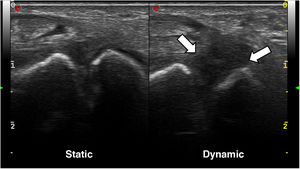

The case presented is that of a 30-year-old left-handed male who consulted for episodes of intermittent chronic pain in the dorsal aspect of the left wrist, which partially subsided after taking anti-inflammatory drugs. The condition began following an accidental fall from his height 2 years earlier, for which he did not consult. A posteroanterior wrist X-ray showed a scapholunate diastasis of 3.5 mm and a rotatory subluxation of the scaphoid (Fig. 1). The study was completed with ultrasound and magnetic resonance imaging (Figs. 2 and 3), which demonstrated a complete rupture of the dorsal component of the scapholunate ligament. The patient was referred to the Hand Unit for consultation, where surgical treatment with arthroscopic ligamentoplasty was decided.

Ultrasound images of the wrist with a high-frequency linear probe; dorsal approach. In the static scan (left image), the scapholunate space appears to be preserved, although a certain hypoechogenicity of the scapholunate ligament can be sensed. However, in the dynamic scan (right image), there is a marked hypoechogenicity with significant scapholunate diastasis, without identifying the ligament with definition, in the context of its rupture.